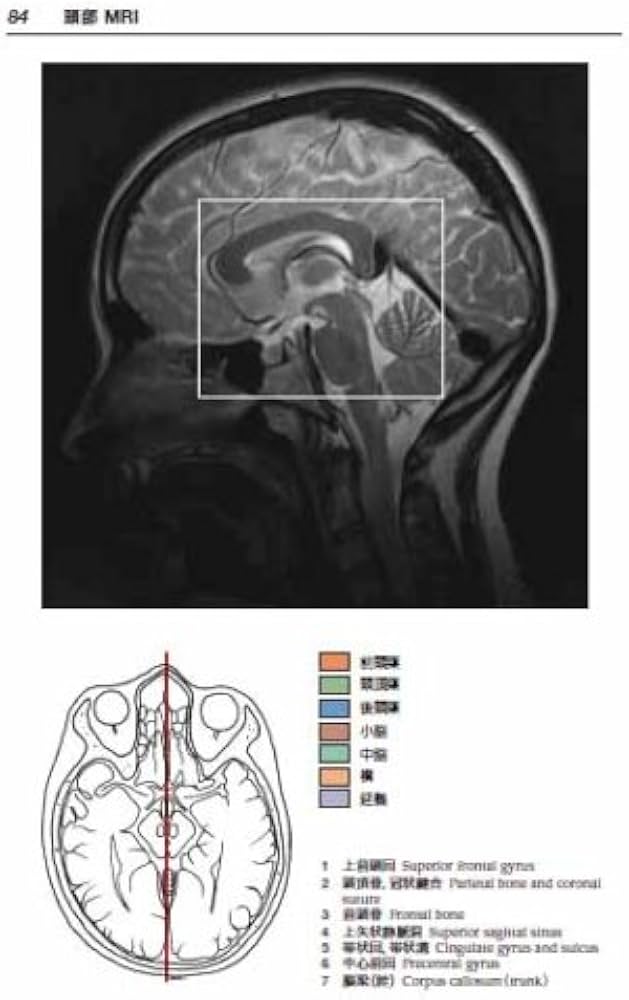

ご覧いただきありがとうございます。\r\r医学専門書\r「頭頸部のCT・MRI 第3版」の出品です。\r\r本書は、頭頸部領域におけるCT・MRI画像診断を詳細に解説した定番の専門書で、解剖・正常像から各種疾患までを体系的に学べる内容となっています。\r\r頭頸部は解剖が複雑で、「どこを見て、何を根拠に判断するのか」が分かりにくい領域ですが、本書では読影の視点や考え方が整理されており、理解が深まりやすい構成です。\r\r研修医の方はもちろん、放射線科医、耳鼻咽喉科医、頭頸部外科など、\r頭頸部画像診断に関わる医療者に幅広くおすすめできる一冊です。\r\r■商品詳細\r著者: 風原博也, 酒井修\r出版社: メディカル・サイエンス・インターナショナル\r裁断・書き込みはありません。\r\r■発送について\r佐川急便/日本郵便(匿名配送)\r水濡れ防止+緩衝材で丁寧に梱包\rご購入後2~3日以内に発送します。\r\r■ご購入前に\r中古本の性質上、多少の使用感はありますが全体的にきれいな状態です。\r即購入OKです。\rご質問があればお気軽にコメントください。